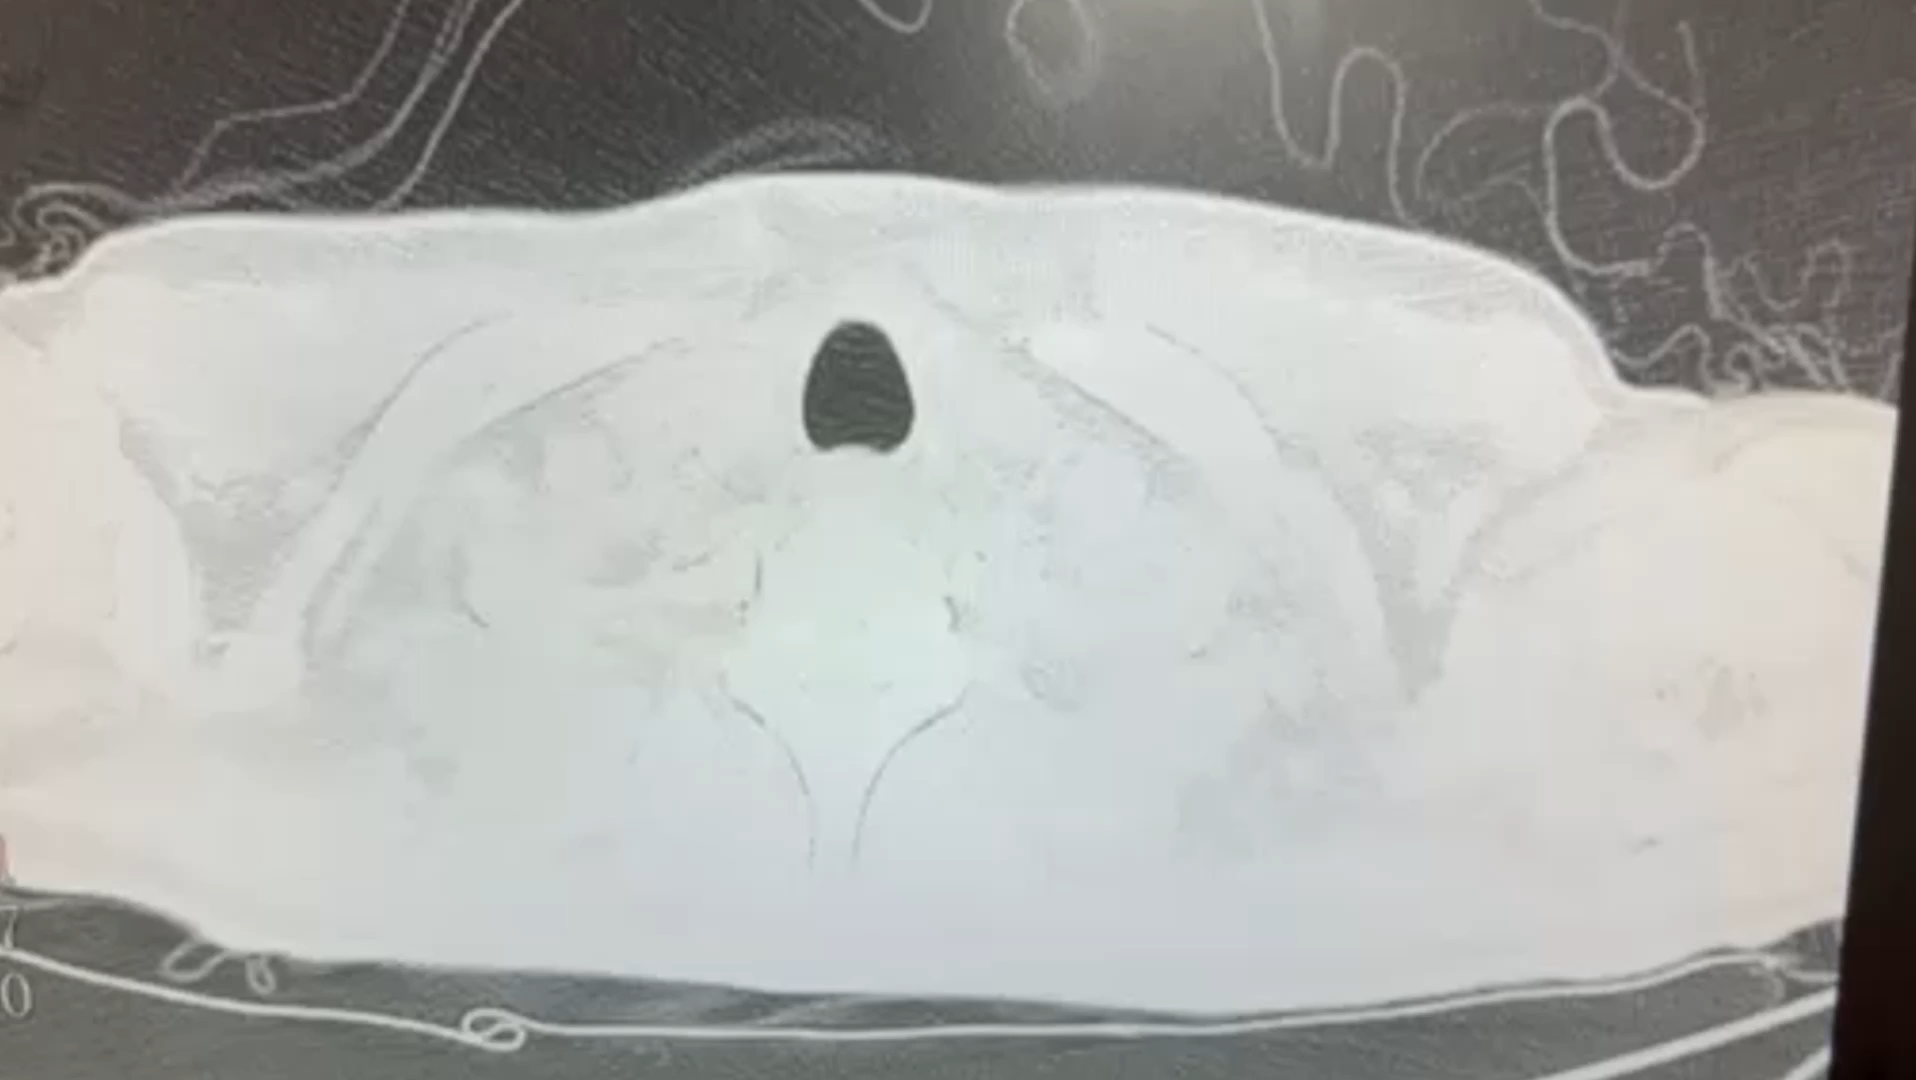

两肺气囊,请秒杀!

CT如下 :

男性,35岁

上腹痛1月伴乏力入院的。

入院诊断为:慢性非萎缩性胃炎(HP+),中度贫血。

查血常规淋巴细胞绝对值0.06*10^9/L,仅60个呀。

HIV抗体阳性,报CDC复核了,复核很慢的,也基本逃不了。

所以最大可能是PJP!